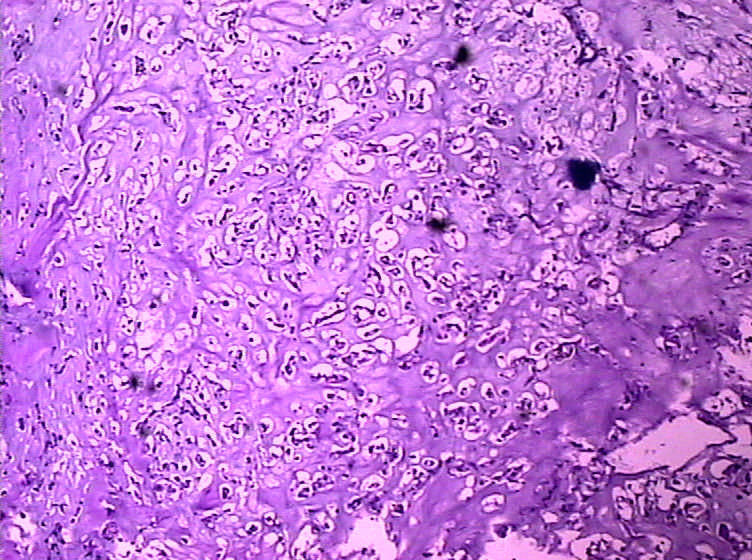

女,4岁,咽喉壁肿物。